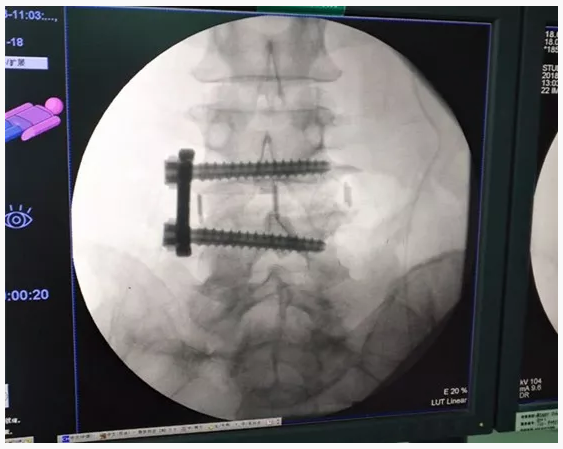

术后

XLIF手术采用单一小切口腹膜后入路完成椎管内间接减压、并进行可靠融合,无需后路内固定,为微创融合提供了又一条解决方案。该技术优势在于允许最大面积与高度的椎间融合器植入,无需剥离牵拉腹膜后大血管与神经,经腹膜后腰大肌肌纤维侧方入路,避免了对腹膜、大血管及神经的过度牵拉及剥离。更为关键的是,XLIF不必切除椎板、关节突关节等维持脊柱结构,避免术后腰背部僵硬疼痛等传统手术并发症。

该技术在我中心的顺利开展,是微创腰椎间融合技术的又一创新与发展,符合现代外科手术微创化的发展潮流。经研究证实,该术式手术创伤小、并发症少,避免了传统后入路内固定带来的二次创伤,在治疗适当的腰椎间盘突出症时,结合我们先进、娴熟的脊柱内镜减压技术、辅助显微镜甚至术中计算机导航,可以做到充分减压和牢固融合,获得满意的临床效果。